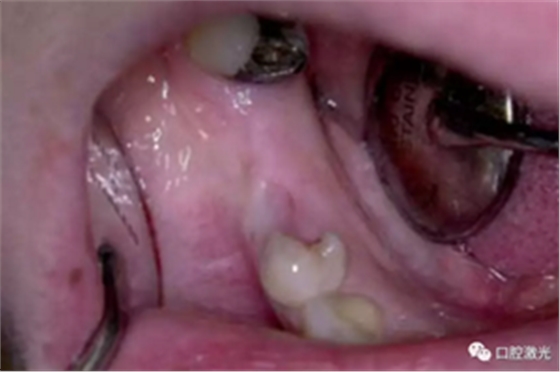

激光辅助治疗术中

术后即刻,薄膜层的形成